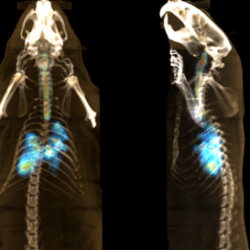

An experiment carried out in Spain shows the distribution of an inhaled nanomedicine in rat lungs.

The PneumoNP project aims at developing new inhaled nanotherapeutic formulations to combat lung infection. The novel drug is comprised of an antibiotic carried by a nanoparticle. For this project, Spanish researchers from CIC BiomaGUNE track the location of the therapeutic particles in rat airways. The use of nanoparticles in formulations is anticipated to lengthen the residence time of the drug in lungs. Indeed, it is expected to slow down and control the release of the active molecules. This prevents rapid metabolism and fast clearance. So, the therapeutic effects are expected to increase. Besides, the delivery by inhalation contributes to diminish undesired toxicological and off-target side effects. The results obtained in imaging experiments are essential to establish the appropriate dosage to be used in therapeutic experiments with infected animals and to predict therapeutic efficacy. The researchers have developed labeling methods to incorporate different radionuclides to the nanocarrier and the antibiotic. Thanks to the different physical properties of the radionuclides, they visualize the spatiotemporal distribution of the nanocarrier and the antibiotic separately. To achieve that they also used complementary in vivo imaging modalities. From imaging experiments, relevant information can be determined quantitatively by using only few experimental animals and extremely refined procedures. The percentage of administered dose that reaches the lungs is important to assess the efficacy of the aerosol delivery method. The researcher looks also for the regional distribution of the antibiotic and the nanocarrier within the lungs. With the spatiotemporal imaging, they evaluated the residence time of the active drug and the nanocarrier in the lungs.